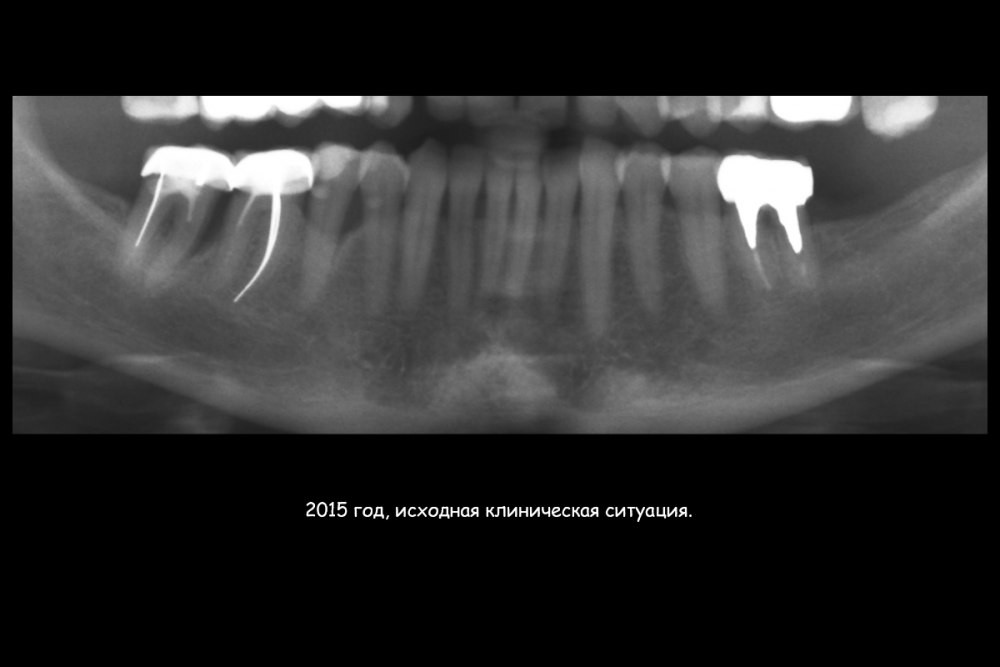

Карен Аванесов Опубликовано 23 июля, 2021 Поделиться Опубликовано 23 июля, 2021 (изменено) Этот пациент особо радует гигиеной на осмотрах, всегда очень чисто, приятно это. Важно когда пациент ответственный. По кейсу все на сгустке крови, без "проленового" рта. Изменено 23 июля, 2021 пользователем Карен Аванесов 6 3 1 Ссылка на комментарий